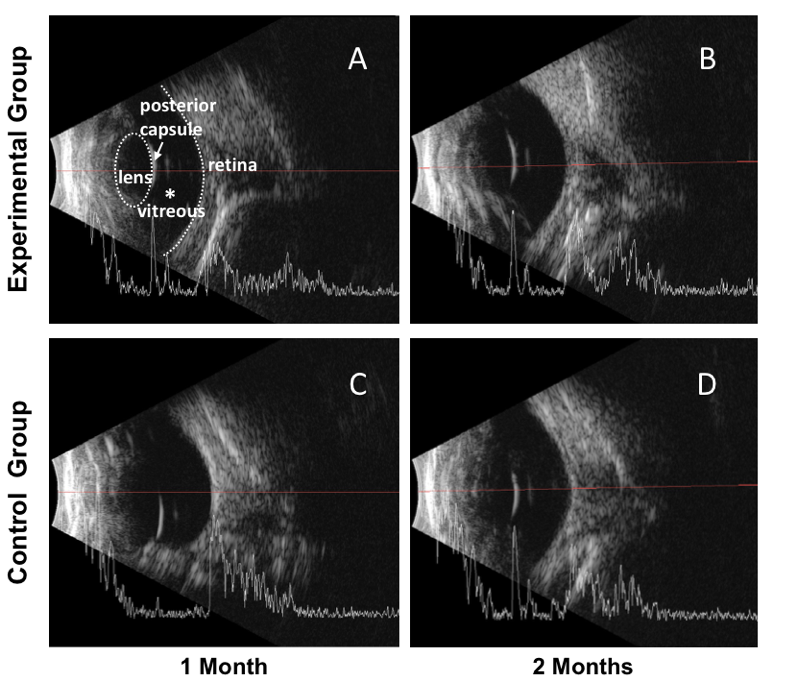

�D 1. DNA������ˮ���z���������˹������w����

�ڴ˻��A�ϣ����о��Mһ������ע�����۲����wǻ����䣬���^��ˮ���z����ۃȵİ�ȫ�Ժ�ҕ�WĤ֧�����ܡ��քe�y���gǰ���g��1�졢1�ܡ�2�ܡ�3�ܡ�1�º�2�Œ��M�����սM���ۉ����g��1�ܕr���g���ۉ��c������Ȳ��o���@����@������DNA������ˮ���z�䪚�صĄ��ԾW��Y������������������ÛЧ�������ˮ���z���������ܽM������~��ĉ��ȣ�Ҳ���������ۉ����ߡ����ǪMխ���P�]���о���ͨ�^�y�������IJ����w��260 nm̎����������ֵ�����g��1����2���µ�DNA�����M�ж������Ķ��u��DNA������ˮ���z���w�ȷ����ԡ����g��2���µĕr�g�ȣ������w��260 nm̎ʼ�K�����^�ߵ��������գ�����DNA������ˮ���z���Է����ؾS���ڲ����w���^�L�r�g���ṩ�־õ����Ч����

��ǰ���z���У�������^�쵽�g�۵��۵׼t�ⷴ�䣬�g�۵Ľ�Ĥ��ǰ���Ͳ����wǻ�Ⱦ�δҊ�����@�������۵יz���У����^�쵽ҕ�WĤƽ����λ��ҕ�P߅��ɫ����ҕ�WĤѪ���������������ϽY��������DNA������ˮ���zչ�F�������õ����������ԣ��]�аl�����Ի��װY������������Ч֧���ۃȽY�������g��1��2�µ��۲�B���Y���У����^�쵽������|ʼ�K͸��������ҕ�WĤ��λ���c����ȱھo���B�ӣ�δҊҕ�WĤÓ�x��ԓ�Y���Mһ���C����DNAˮ���z���鲣���w�����߂����õ����������Ժ����Ч���������ܱ��ֽ��|͸������δ�������wǻ���ᡢ��Ѫ��ҕ�WĤÓ�x�Ȳ��l�Y�� �����g�ۻ֏͡�

�D5. �۲�B���D��(A) ���M�g��1m�������w͸����̓���p͹���ͣ��������w���ҳʸ߻�•�����^����ҕ�WĤ��λ��̓�����ͣ��������w͸������̖����(B)���M�g��2m��(C)���սM�g��1m��(D) ���սM�g��2m��